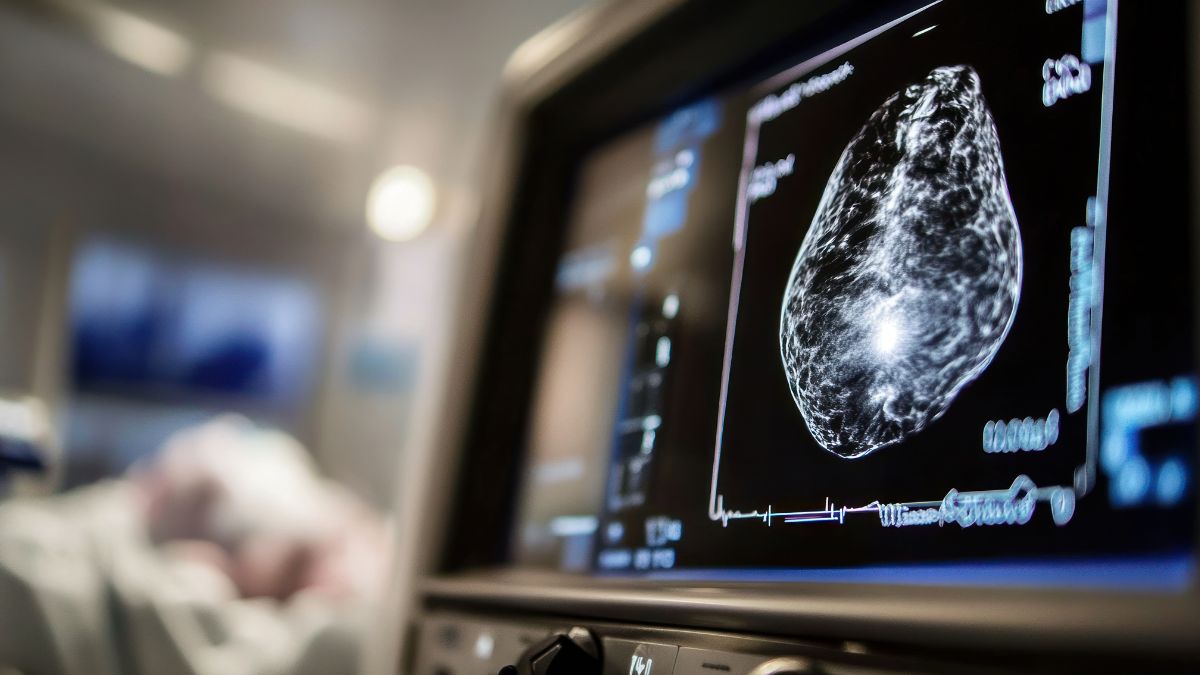

Leczenie uzupełniające inhibitorami CDK4/6 we wczesnym raku HR+/HER2- piersi -praktyczne podejście do oceny ryzyka nawrotu i wyboru leczenia

Od 1 października 2025 roku w polskim programie lekowym w leczeniu uzupełniającym raka piersi luminalnego HER2-ujemnego (HR+/HER2-) dostępne są dwa inhibitory CDK4/6 (iCDK4/6): abemacyklib i rybocyklib. Zgodnie z aktualnymi rekomendacjami ASCO, abemacyklib pozostaje preferowaną opcją u pacjentek spełniających kryteria badań monarchE oraz NATALEE, głównie ze względu na dłuższy okres obserwacji potwierdzający trwałą korzyść kliniczną, obejmującą także przeżycie całkowite oraz krótszy, dwuletni, czas leczenia w porównaniu z trzyletnią terapią rybocyklibem.